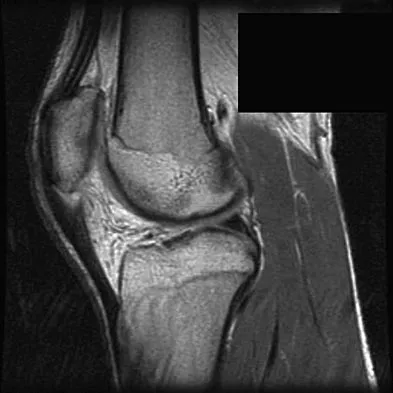

Question 28

Figures 21a through 21c show the MRI scans of a 21-year-old football player who sustained a valgus knee injury while changing direction. Examination reveals swelling and tenderness along the medial aspect of the knee. There is a positive Lachman test, 3+ valgus laxity at 30 degrees, and 1+ valgus laxity at 0 degrees extension. The anterior drawer test is increased with the tibia in external rotation. The increase in the anterior drawer test with the tibia in external rotation is most likely the result of